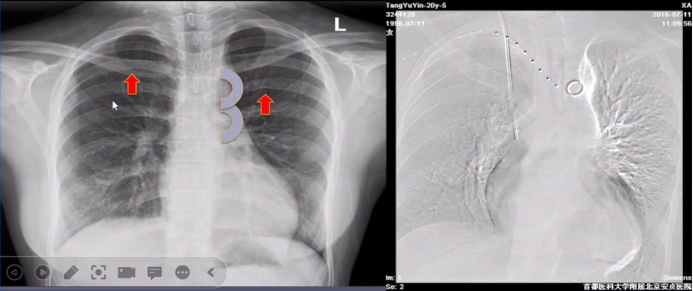

首都医科大学附属北京安贞医院吴文辉教授对青少年及成人先天性主动脉缩窄治疗策略。先天性主动脉缩窄(CoA)是全身动脉病的一部分,而不仅仅是主动脉狭窄,其好发部位通常在无名动脉--第1对肋间动脉间,多位于峡部。病变多呈局限性,也可呈长管状,甚至累及主动脉弓。罕见情况,缩窄位于升主动脉或降主动脉中段。流行病学显示CoA占先天性心脏病7%-14%,男:女约4-5:1,常合并疾病BAV(85%),升主动脉瘤,主动脉瓣上/下狭窄,二尖瓣狭窄,Shone综合征,Tuner综合征。

CMR和CTA是诊断主动脉疾患的有利武器和重要手段,评价主动脉全程,包括缩窄部位,范围,程度,主动脉弓及头部和颈部血管,缩窄前后主动脉情况及侧枝血管情况;还可以发现合并症如主动脉瘤、主动脉夹层,并应用于治疗后随访发现再缩窄、残余缩窄或术后主动脉损伤。

最后,他总结SI(支架植入术)是治疗成人CoA的首选方法,特别适用于变形、成角的缩窄以及有广泛主动脉旁路循环的患者;手术治疗仍然是 CoA 重要的治疗手段,特别是解剖复杂合并动脉瘤、弓发育不良及其它需外科手术干预的并存畸形;CoA合并其它可介入治疗畸形,可一站式处理;CoA合并症的处理应个体化治疗。